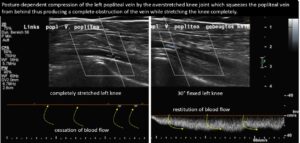

Here the complete compression of her popliteal vein is demonstrated when she fully straightened her knee. Only after flexing her knees to an angle of 30° was her peripetal venous perfusion reinstated.